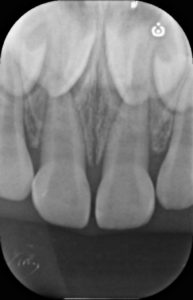

受傷から2週間

脱臼した際に歯の内部の神経・血管に障害が生じるため、内部で充血に伴う歯の変色が生じています。

レントゲン診査でも異常所見はないため、このまま何もせず経過観察を行います。